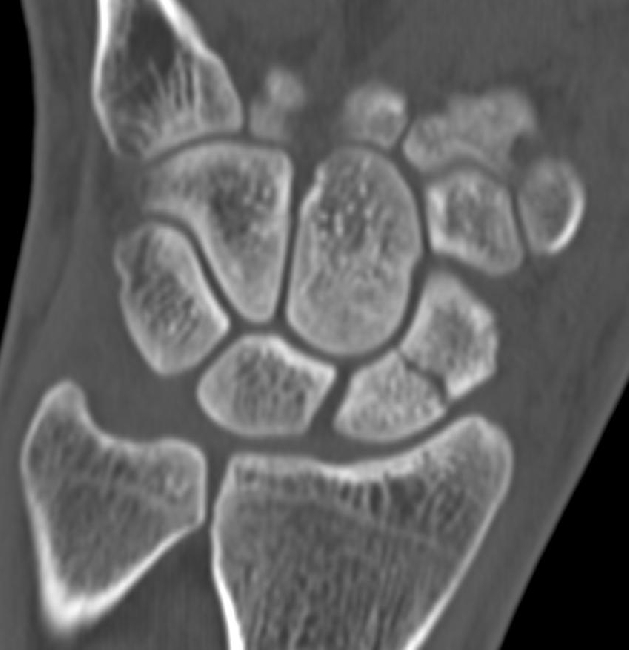

2. Bei der zweiten Untersuchung handelt es sich um

- a) axiale Quellbilder einer CT im Knochenfenster

- b) koronare Rekonstruktionen einer CT im Knochenfenster

- c) sagittale Rekonstruktionen einer CT im Knochenfenster

- d) koronare STIR-Sequenz einer MRT-Untersuchung

- e) sagittale STIR-Sequenz einer MRT-Untersuchung